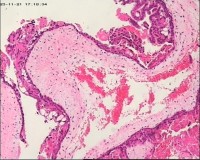

性别

女

年龄

20岁

停经3月,阴道不规则流血7天。

宫刮物

灰白灰红碎组织一堆,大小为7*6*1cm,部分组织呈水泡状

水肿的绒毛和蜕膜,没看到增生的滋养细胞。必要时可做IHC除外部分葡萄胎,并结合临床HCG。

考虑葡萄胎